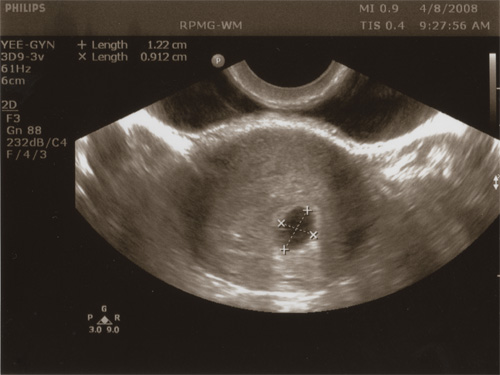

Linda must be getting somewhat tired of having herself poked with various phallic-looking medical devices, but with the aid of one we got a picture of a little something growing inside of her. There was a very pretty picture of a nice little uterus, with a bump in the right place, and a little egg sack in the middle. Our doctor (our infertility doctor, really) was happy to point out the various parts of what we saw, measure the egg sack, etc. We’ve got another appointment for a week from now to look for a visual heartbeat (apparently it’s going to be hard to tell, but it should be a couple of tiny little lines moving up and down).